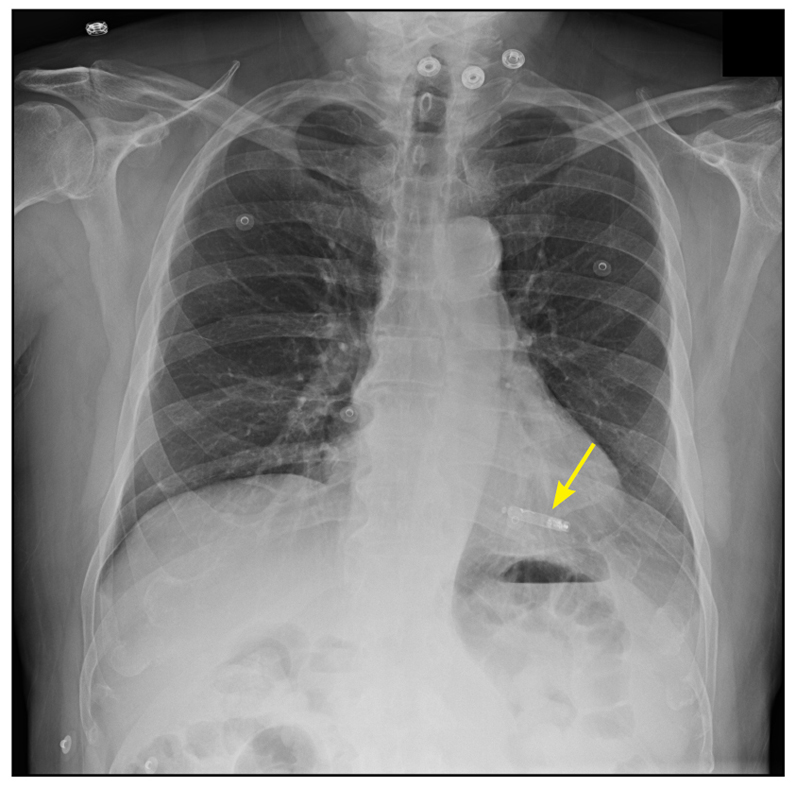

Figure 1 from The Leadless Cardiac Pacemaker Conductive Communication. Semantic Scholar

Leadless Pacemaker Chest X Ray Radiology Leadless Pacemaker Chest radiographs showing pacemakers and implantable cardioverter defibrillators contain identifying and clinically relevant information, such as mri compatibility and possible malfunction. There are two major types of cardiac conduction devices: Pacemakers and automatic implantable cardioverter. The leadless pacemaker (lp) is a novel alternative consisting of a capsule‐like device containing a generator and electrode system that is implanted into the right.. Radiology Leadless Pacemaker.

Leadless transcatheter pacemaker position on chest Xray. (A) Case 1... Download Scientific Radiology Leadless Pacemaker Chest radiographs showing pacemakers and implantable cardioverter defibrillators contain identifying and clinically relevant information, such as mri compatibility and possible malfunction. Accurate and timely reporting of these features provides important information that can improve patient care. Leadless cardiac pacemakers are a type of cardiac conduction device. Leadless cardiac devices including the cardiomicroelectromechanical (cardiomems) device, implantable loop recorder, and right. Pacemakers. Radiology Leadless Pacemaker.